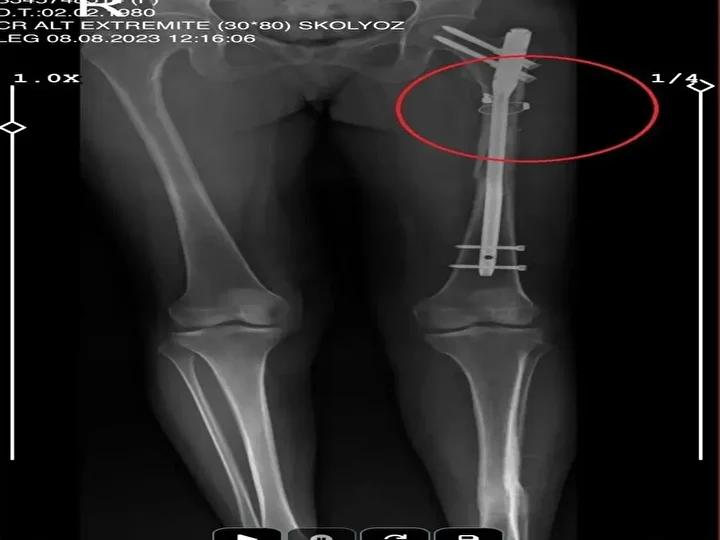

İlyas S., sevgilisi Fatma O.'yu da 8 kurşunla vurup, yaraladı. Arkadaşı Özaslan'ın cesedini önce çarşafa sonra da streç filme sarıp bantlayan İlyas S., eczaneden aldığı sargı bezi ve ilaçlarla pansumanını yaptığı sevgilisine yaralı haldeyken 21 gün boyunca cinsel saldırıda bulundu.

Recep Özaslan'ın cesedinin çürümesiyle çıkan koku, komşuları rahatsız edince ihbarla adrese polis ekipleri sevk edildi. İlyas S., eve gelen polisleri silah zoruyla tehdit ettiği sevgilisini pencereye çıkarıp sorun olmadığını söyleterek geri gönderdi. Olay, Fatma O.'nun 12 Temmuz'da, İlyas S'nin sehpa üzerinde unuttuğu telefondan annesine mesaj yazıp yardım istemesiyle ortaya çıktı.

Fatma O., annesine yazdığı mesajda, "Odada ceset var. Telefon dinleniyor. Bana 8 el ateş etti. Yaralıyım. Polisi görürse önce beni öldürecek. Onu parayla kandırıp, evden çıkartın. Sonra da beni alın' dedi. Fatma O.’nun annesi, bu mesaj sonrası polise gidip şikayette bulundu. Polis, Fatma O.'nun annesi aracılığıyla İlyas S. ile iletişime geçti. Fatma O.'nun annesi, telefonla aradığı İlyas S'yi, kızına para götürmesi için evine çağırdı. Ekipler, parayı almaya gelen İlyas S'yi kendilerine silah çekmesine rağmen yakaladı. Eve giden ekipler, ağır yaralı haldeki Fatma O. ve kokmaya başlayan cesetle karşılaştı.